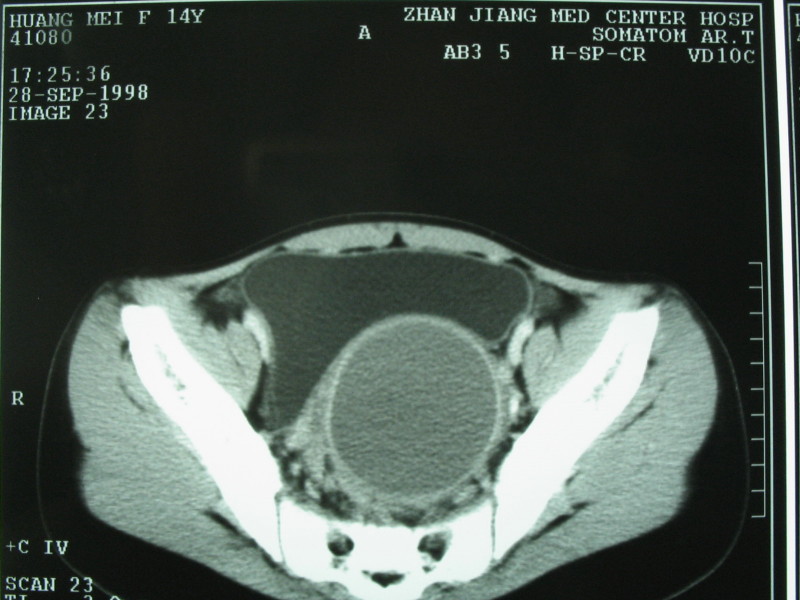

以下是引用xiaoniu在2009-2-13 18:04:00的发言:[br]病变表现在阴道及子宫的位置区,成圆形低密度区,外形光整,建议询问病史来过月经吗,疼痛有规律吗 等,考虑阴道子宫积液或积血,原因应为女性生殖器官发育异常:正常管道形成受阻所致的异常处女膜闭锁

以下是引用随光逐影在2009-2-13 18:13:00的发言:[br]考虑宫腔积液或积血(可能为先天性处女膜闭锁所致,请结合临床检查)。